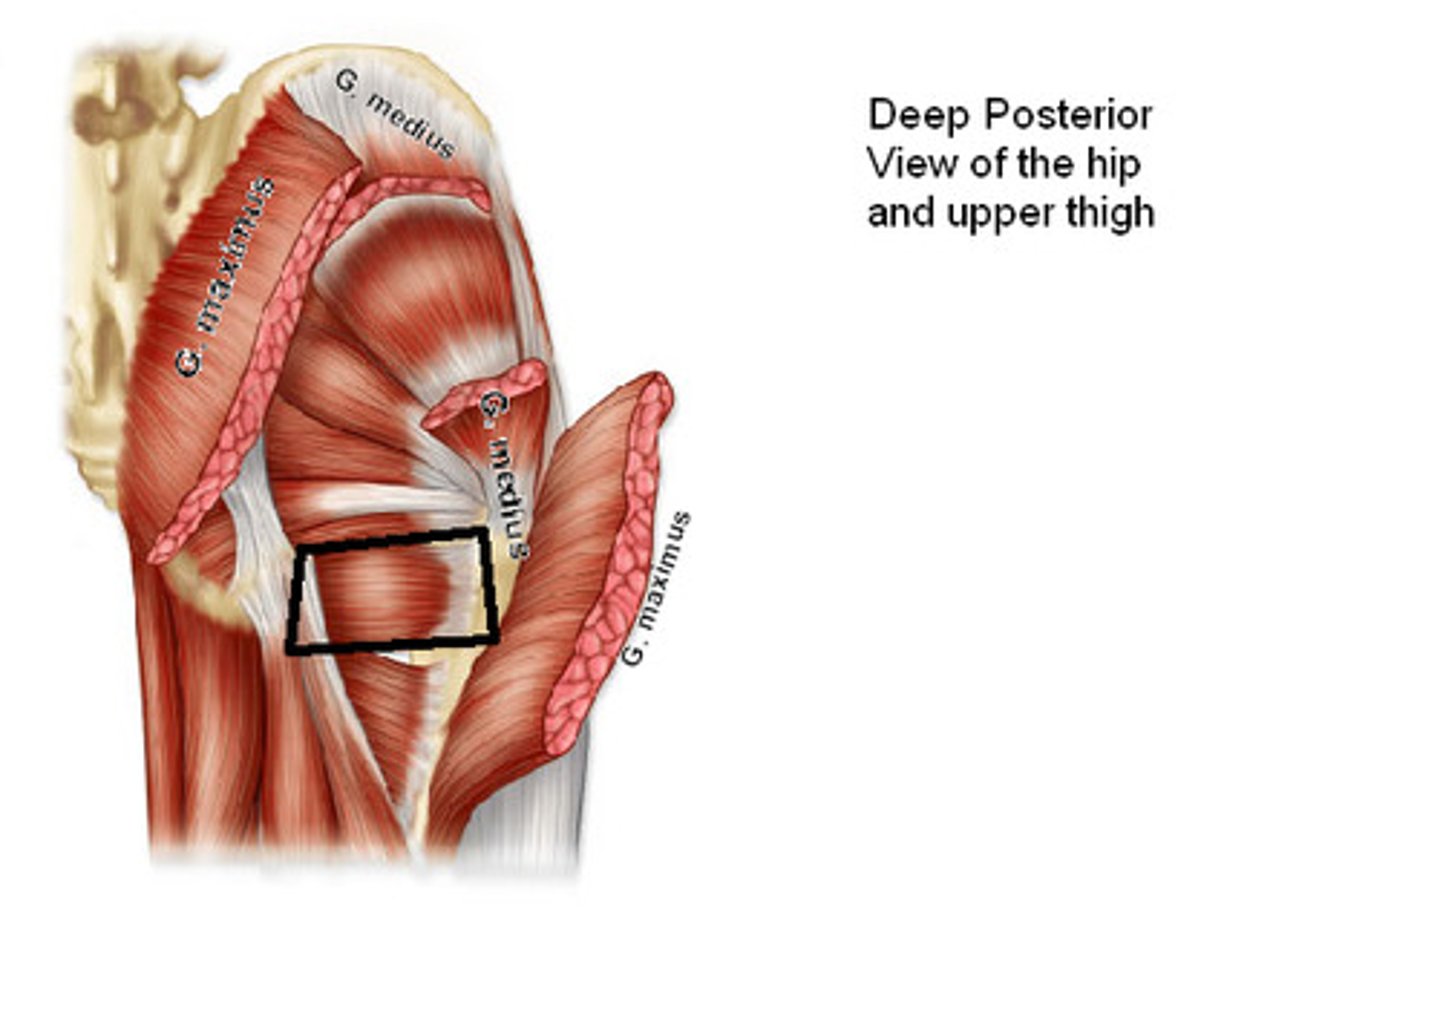

Gluteus maximus m.

Origin: illium/sacrum

Insertion: femur proximal end

Action: extend, rotate

Gluteus medius/minimus m.

Origin: ilium

Insertion: femur proximal end

Action: abduct, rotate

Piriformis m.

Origin: sacrum

Insertion: femur proximal end

Action: abduct, rotate

Obturator internus m.

Origin: obturator foramen edge

Insertion: femur proximal end

Action: abduct, rotate

Sup./inf. gemellus m.

Origin: ischium

Insertion: femur proximal end

Action: abduct, rotate

Quadratus femoris m.

Origin: ischium

Insertion: femur proximal end

Action: abduct, rotate